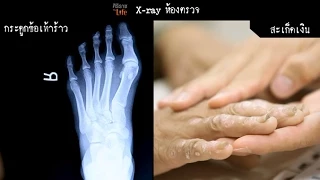

10 อาการอันตรายเสี่ยง เบาหวาน โดนตัดขาไม่รู้ตัว | หมอท๊อป EP 534